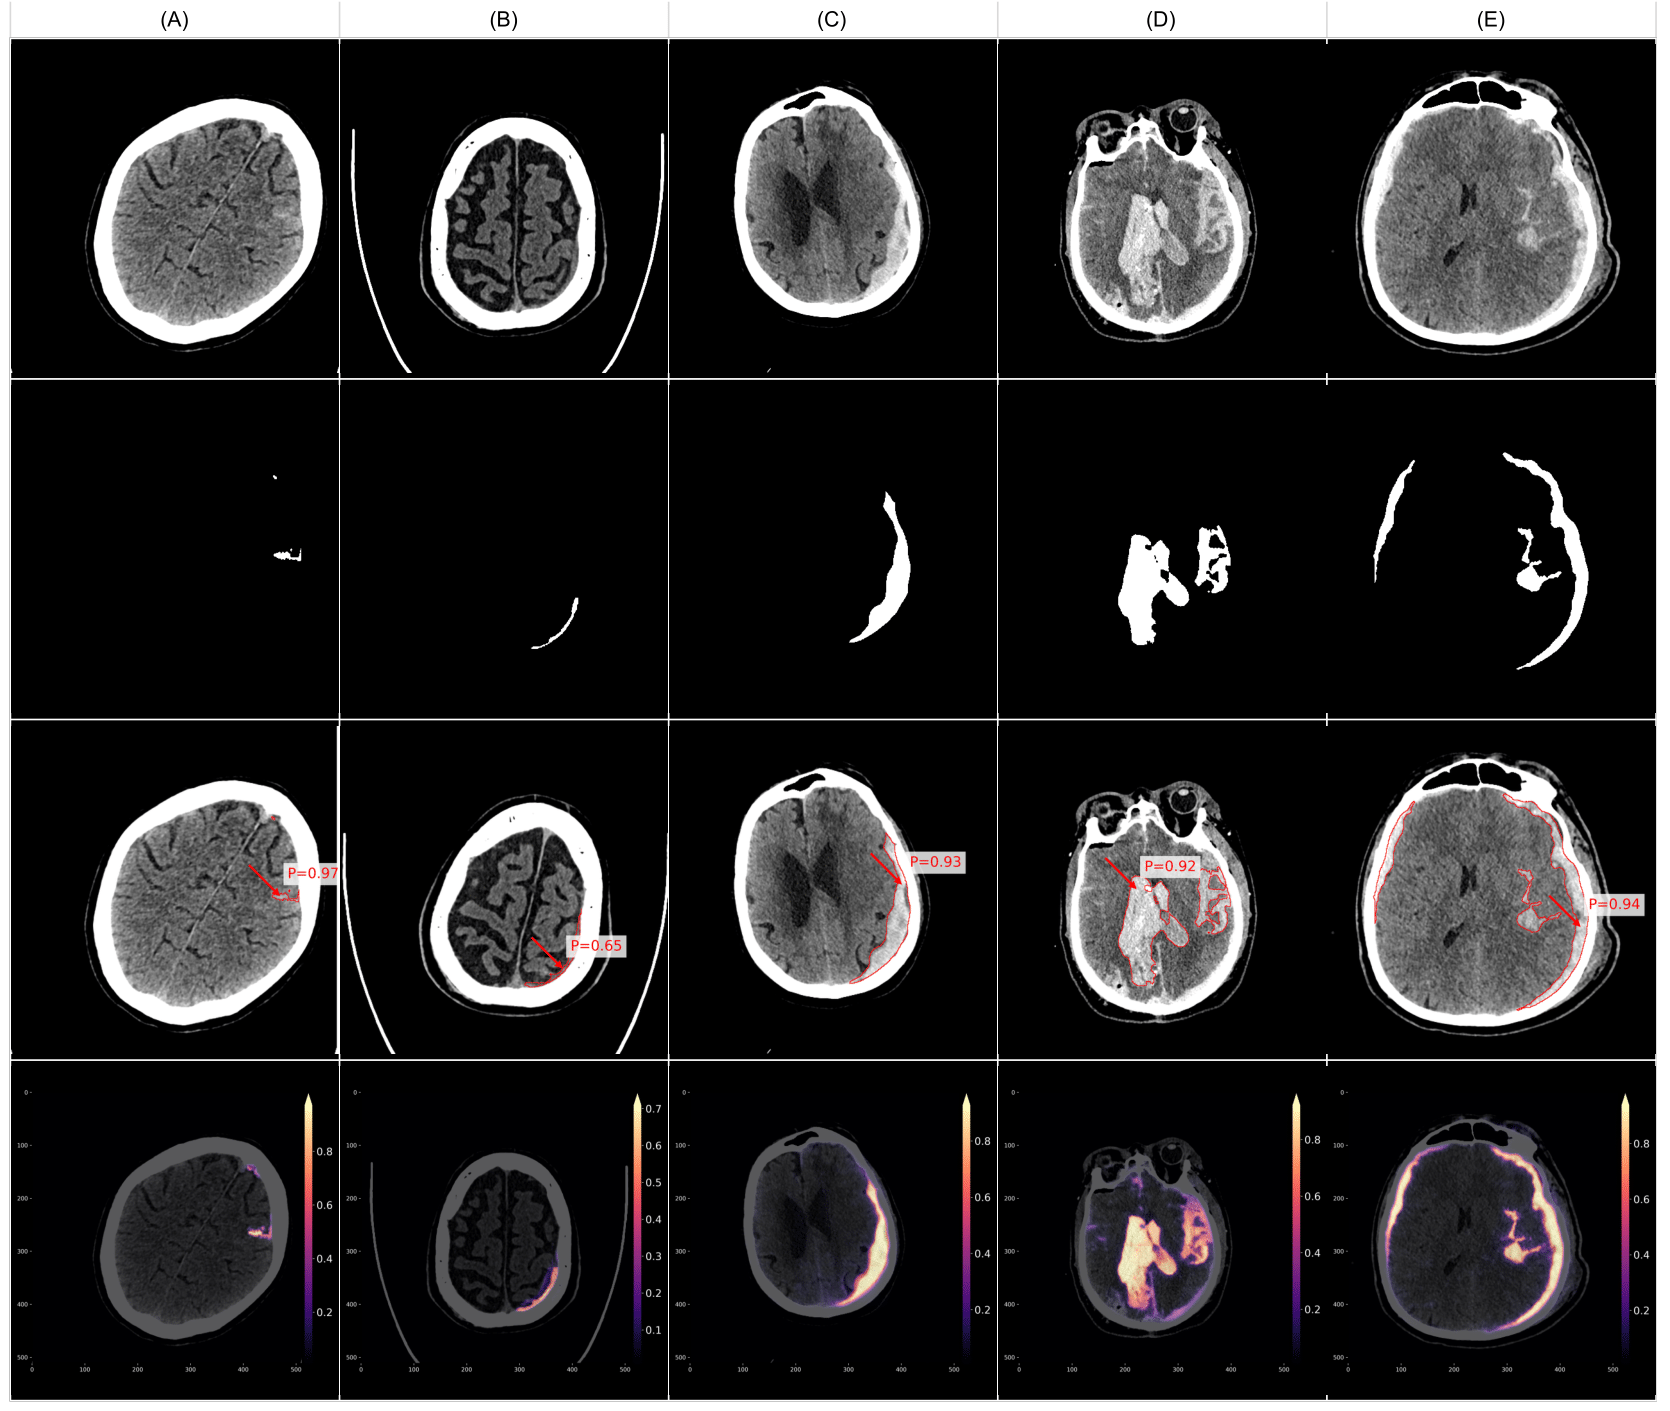

Figure 11 presents examples of false negative cases, where VIOLA-AI failed to detect intracranial hemorrhage (ICH) in CT scans despite the presence of actual bleeds. Although VIOLA identified regions with potential hemorrhage, the predicted bleed probability values fell below the default detection threshold of 0.5, resulting in their exclusion from positive classifications. These false negatives often involve subtle or small bleeds, lesions in anatomically challenging regions, or bleed types that the model struggles to recognize. Addressing these cases is crucial for enhancing the model’s sensitivity, reducing missed diagnoses, and improving patient safety.

Well known challenging factors for both radiologists and AI models are locating and diagnosing; small ICH like SAH and thin SDH right adjacent to the skull shown as examples in Figure 9, but again with error feedback the in-house models can be adjusted to and upgraded especially with an interactive platform like NeoMedSys. To have a high sensitivity often produces a number of false positives, some examples presented in Figure 10, in this dataset the most common presentations were either other pathologies such as tumors or calcifications, or small locations such as close to venous sinuses or calcified/thick dura in the midline. The two latter also pose challenges to radiologists, hence such false positives could be of benefit to bring focus to these areas. False negatives (Figure 11) are always worrisome when it comes to ICH. Detecting bleeds that need acute intervention such as surgery is not difficult for either AI or radiologists to detect, however, the challenge lies with the smaller bleeds, especially the small SAH where studies have shown that they pose no immediate threat to patients, diagnosing these at a later stage does not pose a risk [16]. As false negatives exist eliminates the fact of AI models reliably producing final reports. While our primary focus was overall ICH detection, we acknowledge that a more granular analysis across specific ICH subtypes (e.g., SAH, SDH vs. EDH) will be important in future work as our dataset expands. Furthermore, our deliberate use of a dedicated ’Negative Test Set’ enriched with hard cases was a key strategy to address data imbalance and improve specificity, as reflected in the performance gains from VIOLA-1 to VIOLA-3.